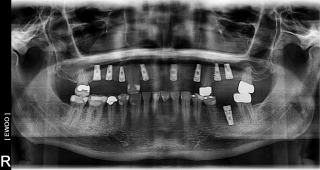

Anthony A.

This patient had only a few remaining infected teeth, but didn’t want to settle for just a denture.  Placed multiple implants and provided a secure fixed option which allowed him to not only chew better but to smile again.